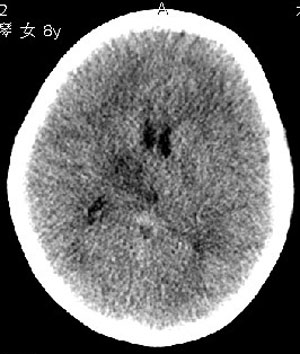

杨某,女,8y,家长述2006.10.13行破伤风疫苗注射后下肢疼痛,后自行粘贴膏药未见好转

,后续发现左上肢肢力下降。于2006.10.28在我院行ct检查,发现右侧基底节区片状低密度影,

无占位效应。ct值约:18~20hu。边界清晰,与相邻脑室无通连。未行增强扫描。余脑实质

未见异常。

右侧内囊后支、丘脑见片状低密度区,边界不清,无占位效应。

从ct图像看,准确地说病变是在右侧丘脑,累积右侧内囊后肢。

因为图像差一些,不能完全排除大脑半球其它区域有无病灶。如果大脑半球其它区域有病灶,则支持脑炎的诊断。有条件应该尽早进行mr检查。